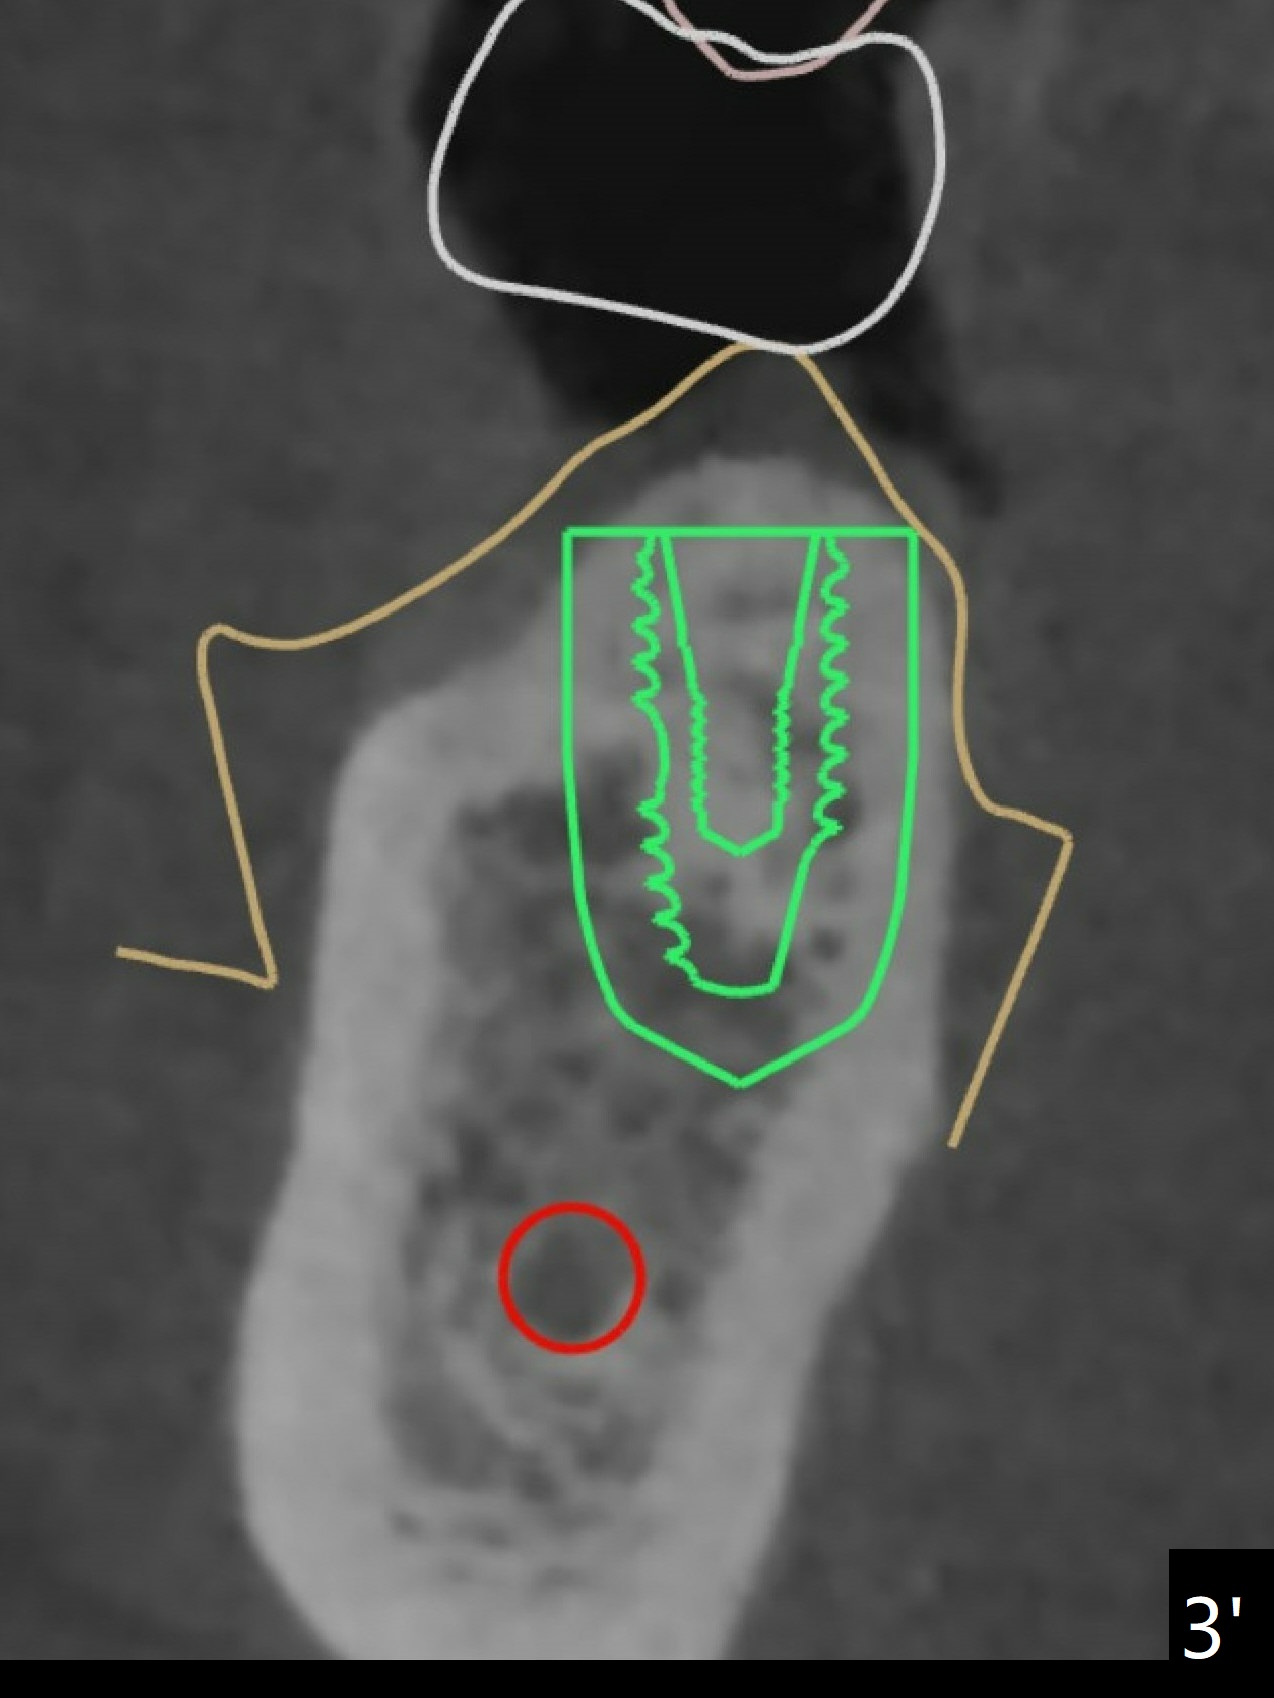

After 4x11.5 mm drill with 10.5 mm offset for bone-level implant at #19, a 4.5x14 mm tissue-level tapered tap is used with high torque. The same sized implant is placed in-completely with apical space (Fig.1 ^). Following reuse of the guide and 4.5x7.3 mm drill, the implant is placed deeper easily (Fig.2-4). The implant threads are subcrestal buccally (B (L: lingual plate), as compared to design in Fig.3'). Later the implant is placed a little deeper with insertion torque of 25 Ncm. There is no crestal bone loss 4 months postop (Fig.5). Waterlase is used for gingivectomy without anesthesia or burn after placing a 4x5 mm abutment. The access is difficult due to severe bone loss. There is no gap between the implant threads (osteointegration) 9 months postop/immediate post cementation (Fig.6 < (coronavirus)), although the crestal bone has lost. After cementation, the tooth #20 has no mobility; note bone loss around the root of #20 (Fig.5). In spite of the residual cement, there appears no bone loss 2 months postop (Fig.7). Instead the distal crestal bone is more organized.